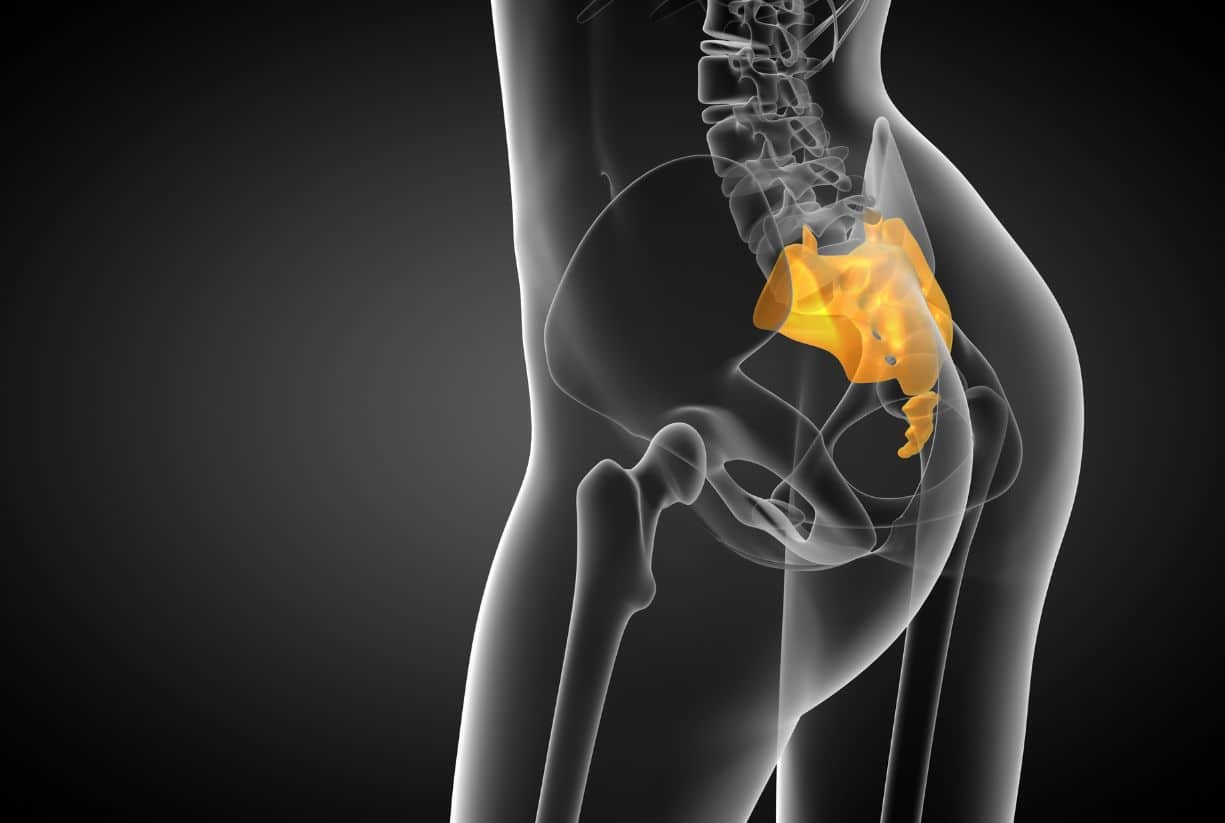

Πονάει η ουρά μου: Ο πόνος στην ουρά (κόκκυγα) μπορεί να προκληθεί από διάφορους λόγους, όπως τραυματισμός, κακή στάση σώματος, φλεγμονές ή ακόμα και παθήσεις που επηρεάζουν τα οστά και τους μυς της περιοχής.

Πιθανά αίτια πόνου στον κόκκυγα

5. Κύστη Κόκκυγα (Πιλονοειδής Κύστη)

Πρόκειται για μια φλεγμονώδη πάθηση που εμφανίζεται στη βάση της σπονδυλικής στήλης και μπορεί να προκαλέσει πόνο, πρήξιμο ή ακόμα και μόλυνση.